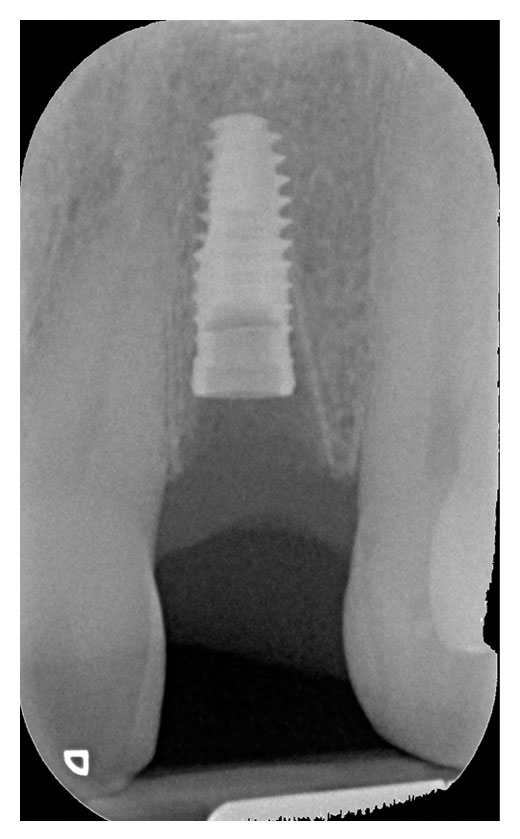

Questa branca si occupa di sostituire le radici perse con strutture in titanio che supportano elementi protesici. Grazie agli impianti è possibile sostituire denti singoli, intere arcate, selle edentule, stabilizzare dentiere.

Con l’apporto della chirurgia computer guidata in carico immediato la riabilitazione si realizza in poche ore e con un minimo disconfort post operatorio.